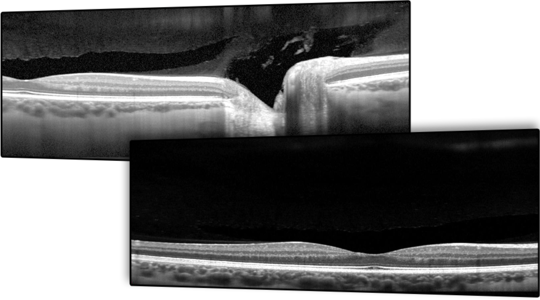

11.Módulo Flex

Imagem diagnóstica flexível para pacientes em posição supina

O Módulo Flex para SPECTRALIS®, a plataforma multimodal de imagem diagnóstica para o segmento posterior, permite que clínicos e pesquisadores realizem exames de imagem em pacientes que não podem se apresentar em uma posição estática, com apoio para cabeça montado na mesa. Com o Módulo Flex, o SPECTRALIS é fixado em um suporte móvel com braço ajustável. Ele oferece um grau de flexibilidade que vai muito além da imagem oftálmica convencional, estendendo toda a funcionalidade multimodal diagnóstica para várias posições e ambientes de aquisição. É mais adequado para aplicações clínicas que exigem maior mobilidade.

O Módulo Flex permite realizar exames oftálmicos em pacientes em posição supina, pacientes com doenças sistêmicas, pacientes pediátricos e também para monitorar os resultados de cirurgias oculares. Utilize todas as tecnologias e modalidades de imagem do SPECTRALIS – desde OCT até imagens de fundo de olho por laser de varredura e angiografia – para realizar exames móveis sem sacrificar a qualidade da imagem.

Uma bateria de backup opcional permite 20 minutos adicionais de autonomia para evitar interrupções ao mover o dispositivo entre tomadas de energia. Isso resulta em flexibilidade de modalidades e mobilidade espacial que não pode ser alcançada com nenhum outro dispositivo. Ao mesmo tempo, ele pode ser mais estável do que dispositivos OCT manuais, fornecendo um SPECTRALIS móvel com todas as funcionalidades necessárias para exames completos e convenientes, que, por fim, melhoram o cuidado do paciente, especialmente para aqueles que não podem sentar-se de maneira ereta.